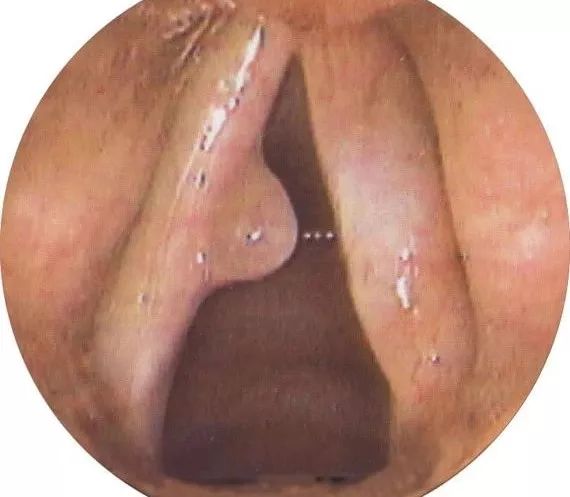

声带息肉在临床上比较常见,病因尚不十分清楚,可能与长期发声不当、长期不良刺激或慢性炎症有关。主要表现为声嘶,嘶哑程度因息肉大小和部位不同而异,轻者仅有轻微声音改变,重者嘶哑明显甚至发声困难。

声带息肉不仅可影响正常生活和工作,若息肉较大阻塞喉腔,可引起呼吸困难。

声带息肉的致命杀伤力在于突发癌变。

但很多息肉在癌变后,患者并没有很强不适感,息肉就不知不觉发展,甚至癌变。

因此,一旦出现声音嘶哑、喉部异物感、咽喉干痒疼痛,建议立即到医院做纤维喉镜明确诊断,必要时也可在医生建议下做手术摘除。